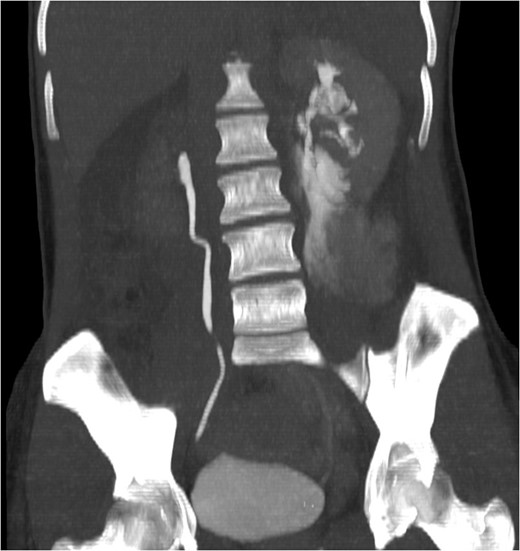

CT IVU- confirmed extravasation of contrast medium around the left kidney and ureter, the rupture being at the level of the PUJ.

Coronal view reconstructions using maximum intensity projection, showing proximal ureteric leak of contrast.